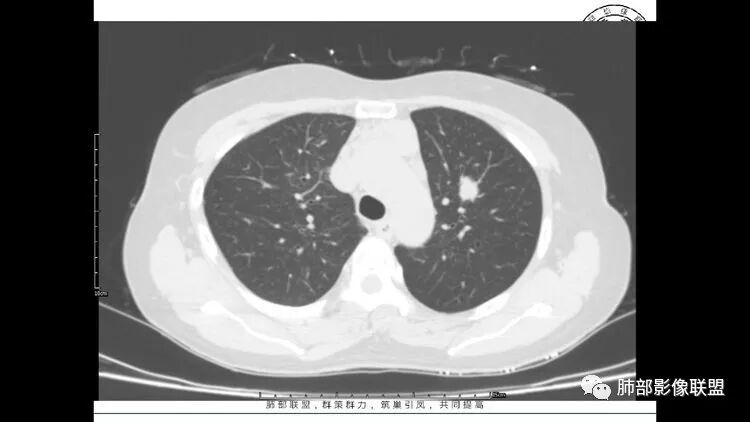

老年女性,眼炎入院,血常规正常,双肺多发囊状影,病变随机分布,形态单一,与血管关系密切,考虑LIP。左下肺混合GGO,边界尚清,贴近囊腔,鉴别腺癌。炎症指标无异常暂不考虑感染性病变。

胸CT:1.双肺多发囊性变,以中下肺为主,病变边缘可见肺动脉,部分囊内可见分隔及肺动脉,双下部分肺野周围可见小叶中心结节及树丫征。

2 左肺上叶尖后段 右肺上叶前段 右肺下叶外基底段 结节影,边界清楚,可见柔软毛刺,左肺下叶后基底段混合密度影。

3.纵隔淋巴结肿大?,以主动脉弓为界向上向下增大。

双肺下叶分布为主的间质改变(磨玻璃影、小叶间隔增厚)、散在气囊影(常有血管贴边)、边界不清小结节